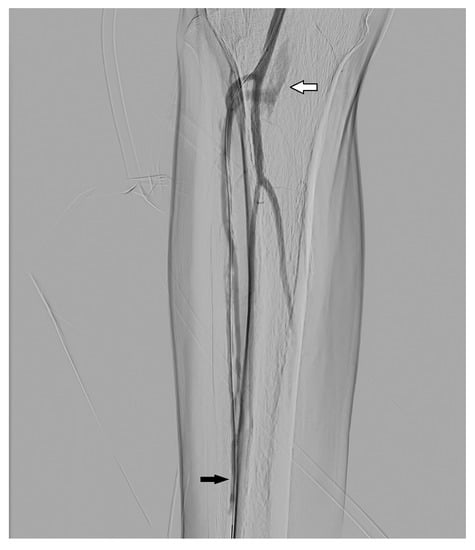

3.2. Dissection